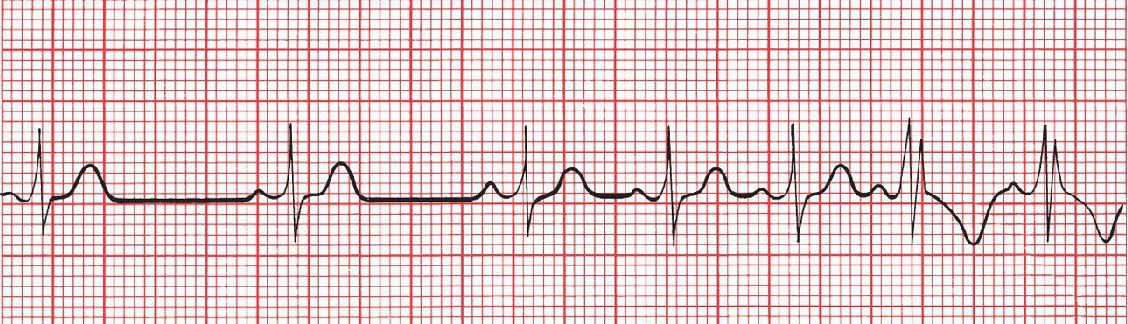

Compare the following two, what types of block are they?

(A) Wenckebach block, with progressive lengthening of the PR interval. (B) Mobitz type II block, in which the PR interval is constant.